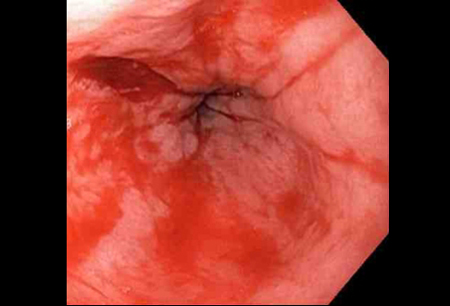

Bleeding Mallory Weiss Tear viewed on retroflexion

From the personal collection of Douglas Adler; used with permission